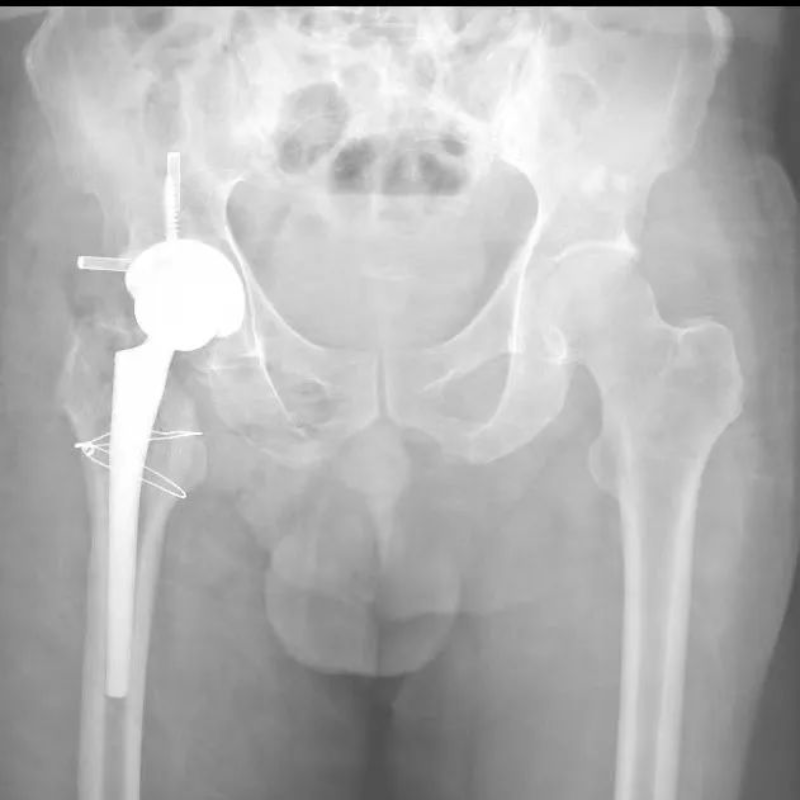

50多岁的朱大哥,20多年前因为车祸伤导致股骨头缺血性坏死,一直一瘸一拐走路,就诊时,右侧髋关节股骨头基本消失,髋臼磨损严重,关节已接近融合,肢体短缩有6-7cm,通过术前AI规划,能精准确定截骨的位置,髋臼杯安放的角度和尺寸等。手术进展顺利,术后关节功能恢复良好,肢体短缩明显纠正无神经损伤等并发症,一个月后复查关节稳定,患者从此告别一瘸一拐的日子。

△术后